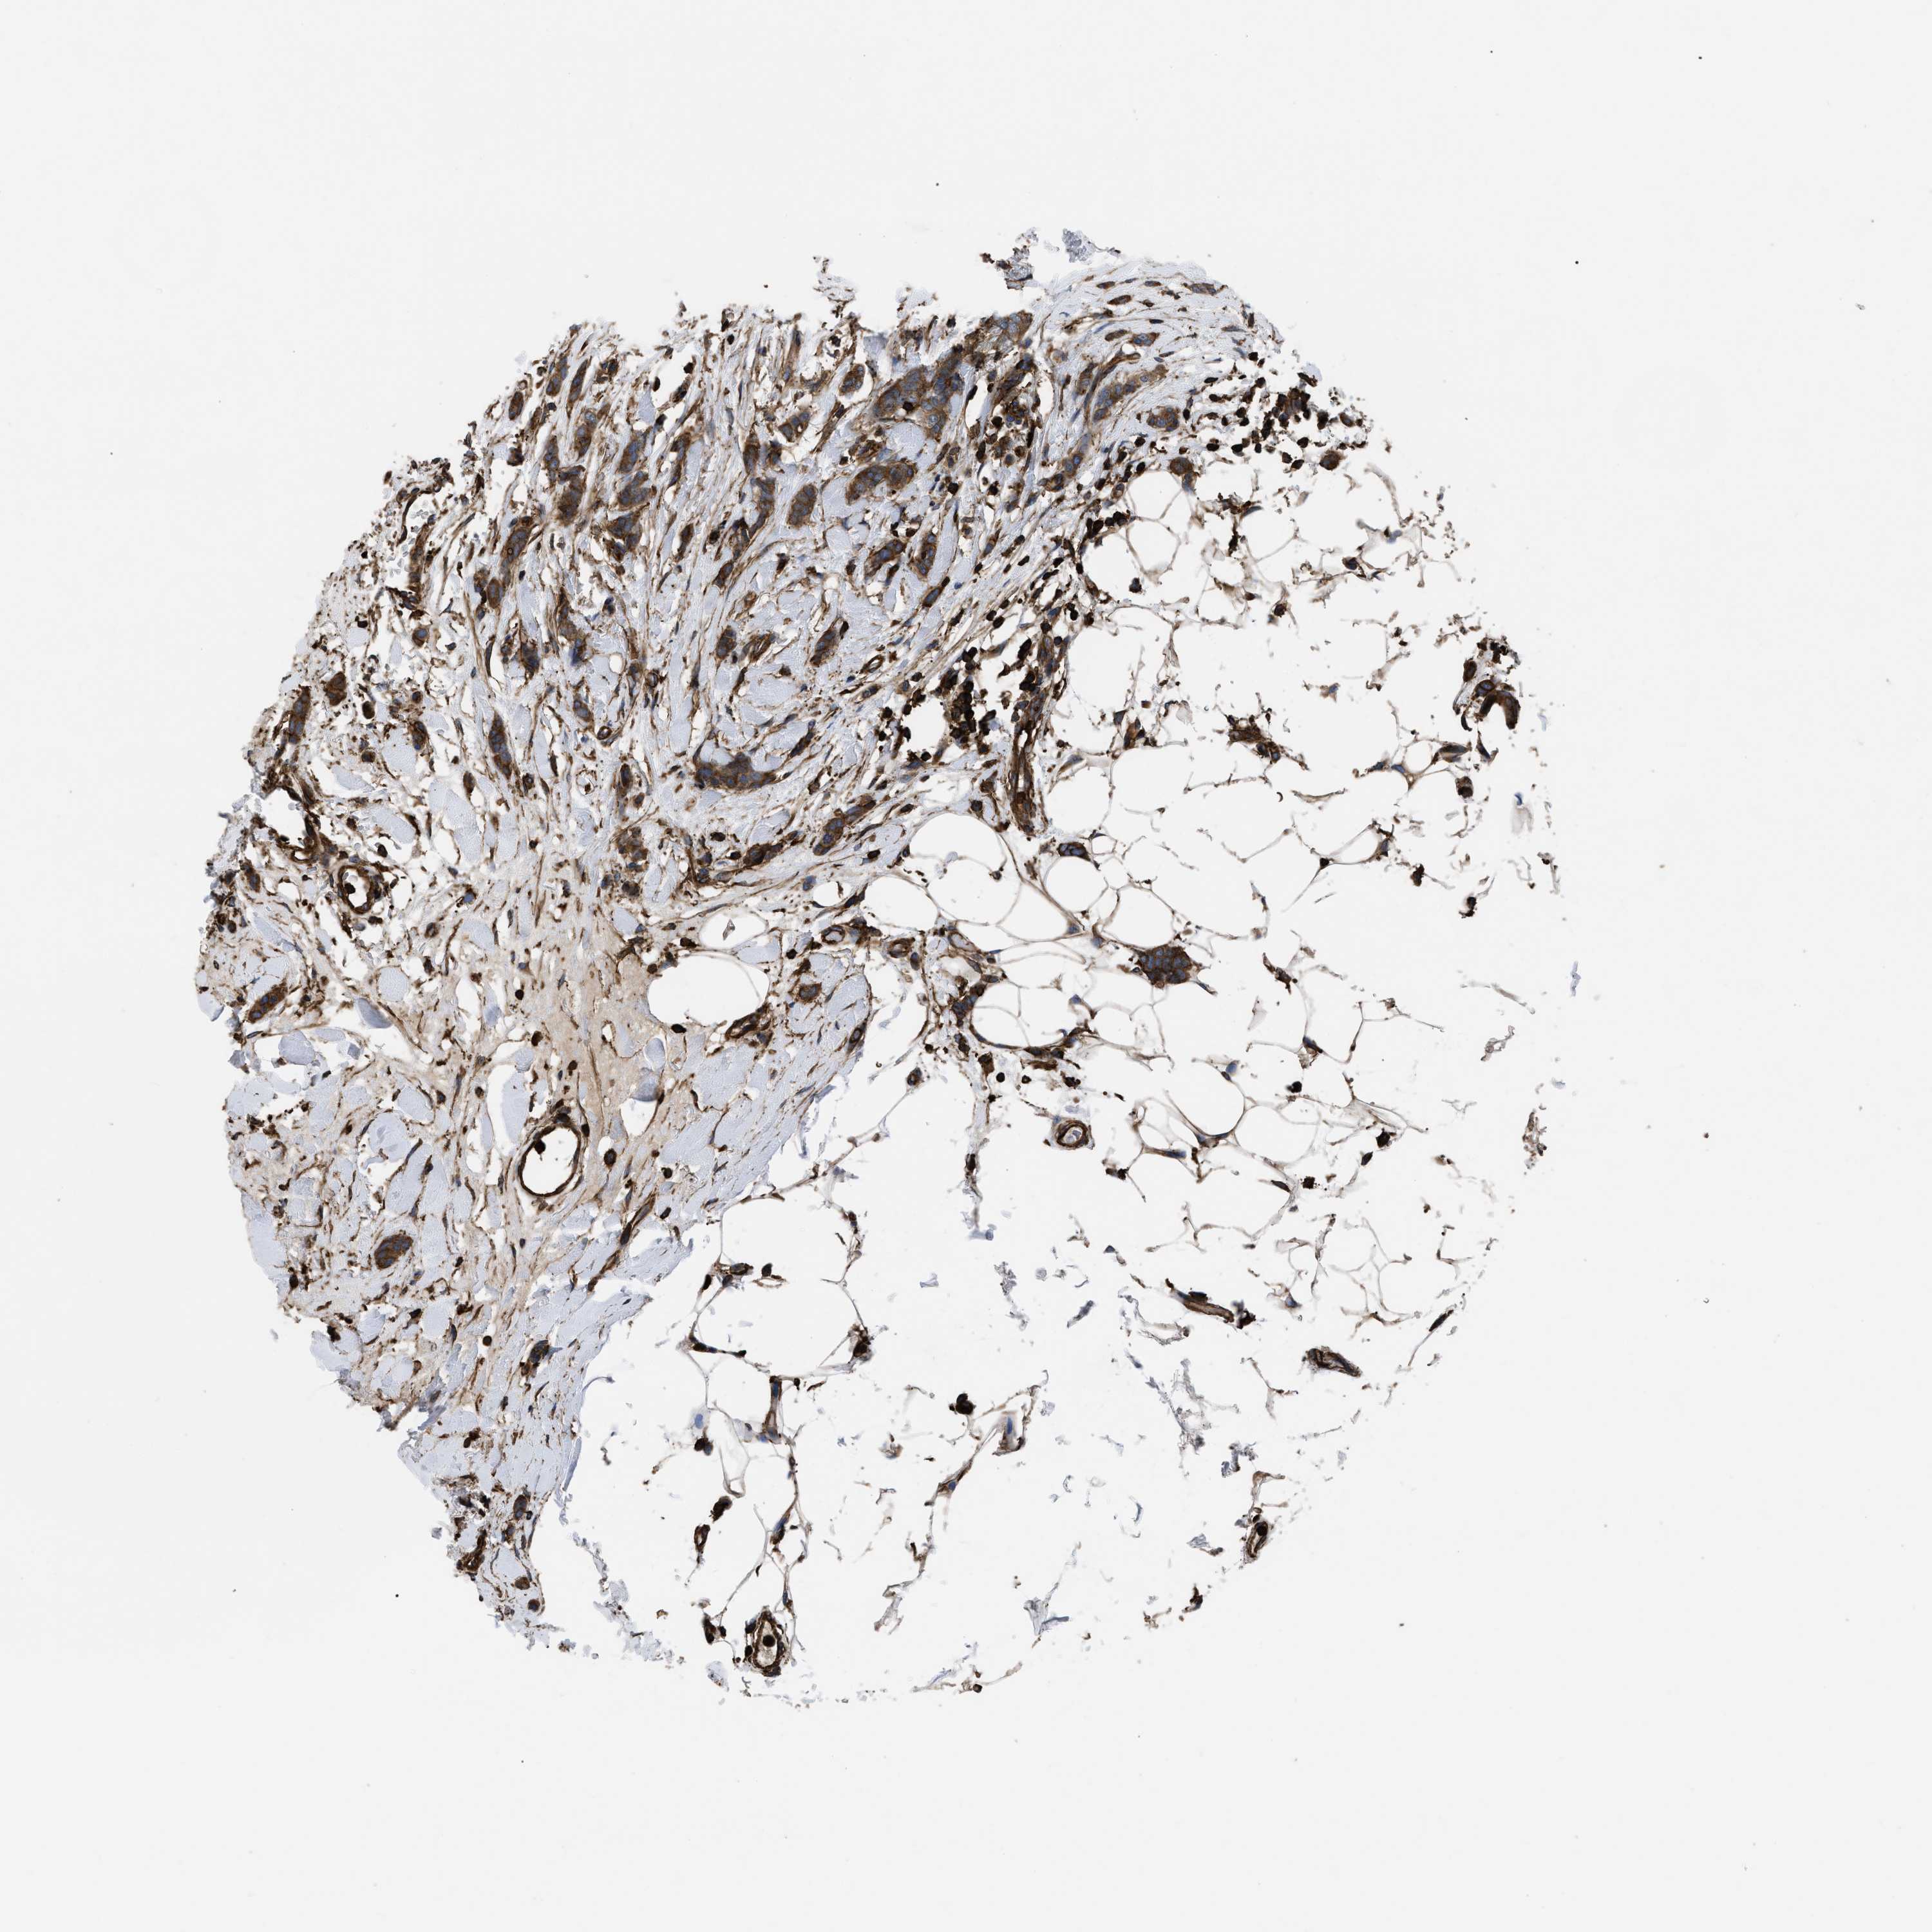

BRCA TCGA BRCA VALIDATION PROTEIN EXPRESSION